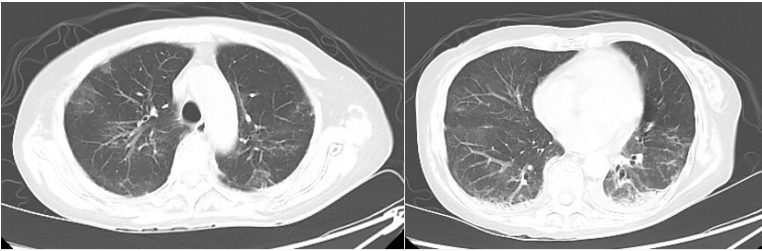

复查胸部CT可见病灶明显吸收(图8)

图片

图8  患者治疗前后胸部CT比较